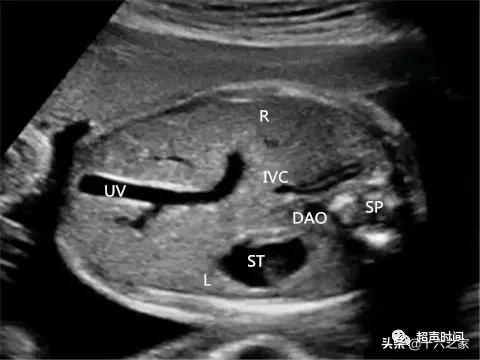

图 11 正常腹部横切面显示下腔静脉( IVC )

若此切面发现下腔静脉消失或奇静脉增宽 , 则应重点观察是否存在内脏异位及心脏畸形;并对继续妊娠孕妇跟踪随访 , 产后可对新生儿行超声联合 CT 检查 。

- 上腹部横切面图:显示下腔静脉与腹主动脉在脊柱两侧的对称关系消失 , 腹主动脉右后方为扩张的奇静脉 , 而无肝段下腔静脉;